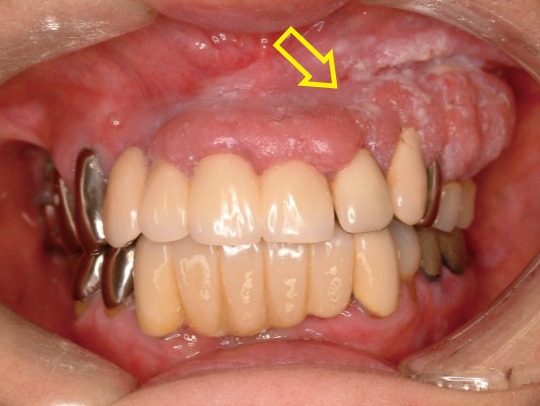

この段階のがん患者は症状を感じない場合があります。初期段階の唇がんの症状の 1 つは、唇の赤または白の斑点です。

ステージ 1 の口唇がんには、他の場所に転移していない大きさ 2 cm 未満の原発腫瘍があります。腫瘍は、肌の色が明るい人にとっては赤いただれのように見え、肌の色が濃い人にとっては暗褐色または灰色のただれのように見えることがあります。